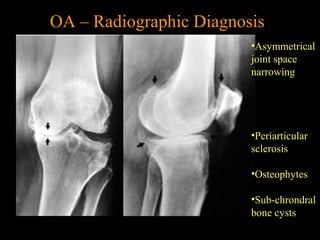

Asymmetrical joint space narrowing from loss of

articular cartilage

The medial (inside) part of the knee is most commonly affected by osteoarthritis.

OA – Radiographic Diagnosis

•Asymmetrical

joint space

narrowing

•Periarticular

sclerosis

•Osteophytes

•Sub-chrondral

bone cysts